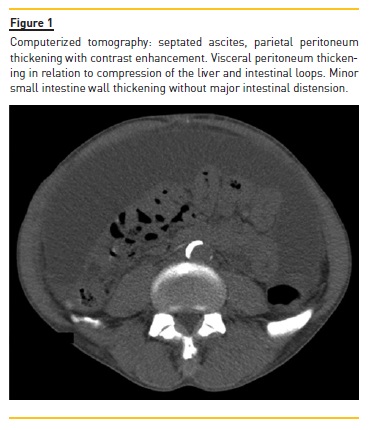

In summary, a previously stable male HD patient presented to the hospital with fever, anorexia, increased abdominal volume, worsening anemia, increased inflammatory markers, septated ascites, and visceral peritoneal thickening of the intestinal loops. The embedded PD catheter was exteriorized and hemoperitoneum was confirmed. Thus, a diagnosis of EPS was considered. Treatment was initiated with daily peritoneal lavage, oral nutritional support, oral prednisolone 0.5 mg/kg/day (6 days), and tamoxifen 20 mg every 12 h. The patient presented complete resolution of the symptoms and regularization of inflammatory markers over the following days. A second CT showed less peritoneal contrast enhancement, less heterogeneity of the intraperitoneal fluid, disappearance of septated ascites, and persistence of minor small intestine thickening (Figure 2).). Despite losing weight during admission, the patient recovered appetite and was discharged on oral prednisolone and tamoxifen, with 58.2 kg. The patient received nutritional counseling from a dietician at the hemodialysis clinic, initiated a hypercaloric diet and his condition was regularly evaluated.